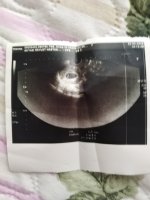

Canım bunlar Altan gözüktü sadece baş popo mesafesj var crl diye 6+4 pko olduğu için geç döllenme daha gitmedm doktora kalp atisii icin 7+7 yiz bugün

• IMG_20220429_113644.jpg

IMG_20220429_113644.jpg

2.5 MB · Görüntüleme: 187